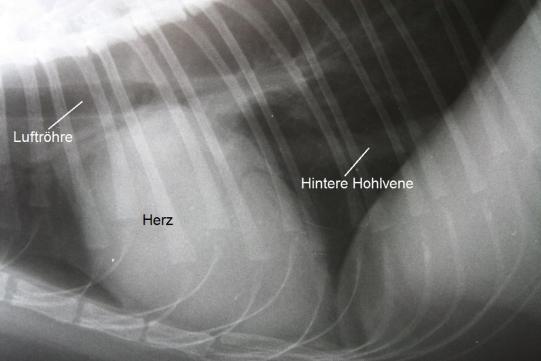

Schon in der Nacht wurden Röntgenbilder des Brustkorbes angefertigt, welche ein vergrössertes Herz mit übermässig grossen Vorhöfen zeigt.

Die Röntgenbilder weisen auf eine Herzerkrankung hin, welche zum Verschluss der Körperschlagader geführt haben könnte. Das Herz wird mittels Ultraschall genauer untersucht, und es zeigt sich, dass die Muskulatur der Herzkammern sehr stark verdickt und die Vorhöfe stark erweitert sind. Eine Diagnose einer Hypertrophen Kardiomyopathie (HCM) wird gestellt.